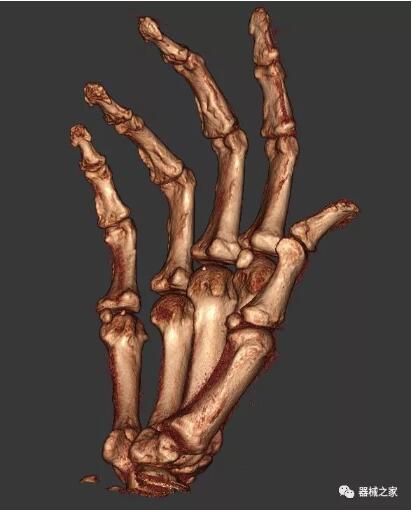

以上介紹的CT均來自國外同一家公司,這些CT均配置了可視化軟件,可以進(jìn)行切片、3D重建以及大型CT附帶的所有典型的操作功能。

當(dāng)然,這類充滿想象力的CT,國內(nèi)也有生產(chǎn)廠家在研究,比如賽諾威盛研發(fā)的InsitumCT Zero,可以很好的適應(yīng)特殊的臨床應(yīng)用場景,超大孔徑多種自由度組合,可實(shí)現(xiàn)水平和垂直等多種掃描模式。

對于急診外傷患者,它縮短了診斷到治療的路徑,避免移動患者帶來的二次損傷;復(fù)合手術(shù)室中,它可以讓醫(yī)生第一時間確認(rèn)或調(diào)整手術(shù)方案,大大縮短手術(shù)時間;對于需要放療定位、質(zhì)子治療的患者,一站式的定位、治療服務(wù)能夠更加精準(zhǔn)。

以下是這些“特立獨(dú)行”的CT所拍出來的圖像: